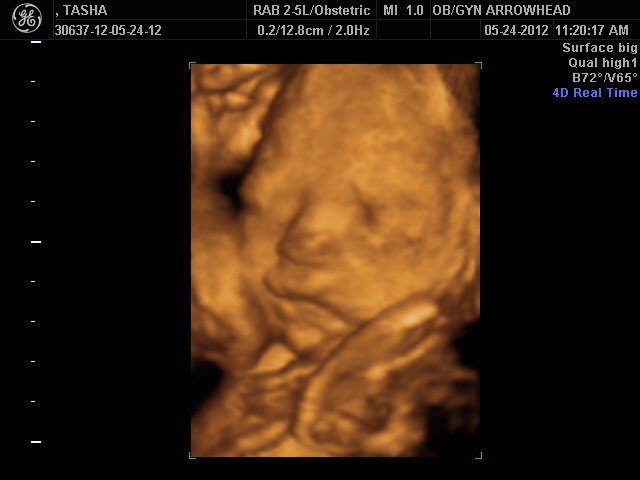

We offer complimentary 3D/4D Ultrasounds to all our OB patients around 30 weeks! The following photos are some examples of our work, shown with permission from our patients.